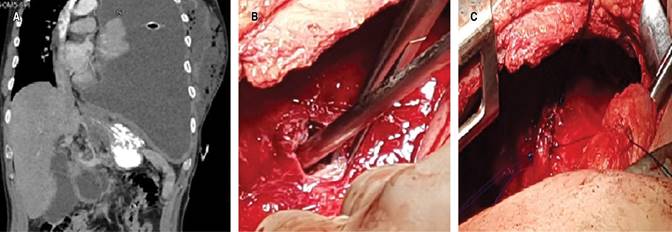

Caso clínico 1. Hombre de 39 años, con antecedente de alcoholismo crónico, con episodios de dolor abdominal recurrente. Inició su padecimiento tres meses previos a su ingreso, con dolor pleurítico en hemitórax izquierdo, se agregó disnea progresiva y ataque al estado general; se tomó radiografía de tórax en la cual se identificó derrame pleural. Se realizó toracocentesis y se obtuvo líquido pleural de aspecto oscuro, espeso; mismo que, al análisis citológico y citoquímico, presentó cifras de amilasa en 16,043 U/L y con criterios de Light de exudado neutrofílico. Posteriormente, al realizar tomografía axial computarizada (TAC) de tórax y abdomen (Figura 1A), se identificó comunicación de líquido libre del abdomen con el hemitórax izquierdo, por lo que se decidió llevar al paciente a la sala de quirófano para realizar toracotomía posterolateral; se encuentra pleura parietal con grosor de 8 mm y visceral de 5 mm, abundante material de fibrina y pus en cavidad, un trayecto fistuloso entre la cavidad abdominal y diafragma izquierdo de 1 cm de diámetro (Figura 1B), con colección de 100 mL de líquido blanquecino. Se realizó lavado y decorticación hasta lograr adecuada expansión pulmonar, el trayecto fistuloso se desbridó; se identificaron bordes y se realizó cierre del defecto con sutura no absorbible de polipropileno 2/0 (Figura 1C); se verificó reexpansión pulmonar. Posterior al tratamiento, el paciente cursó con adecuada evolución clínica; los drenajes endopleurales, con gasto serohemático que disminuyó hasta su retiro cinco días después del procedimiento. Se realizó TAC de control, la cual mostró disminución de la colección pancreática inicial. Después de valoración por el Servicio de Gastroenterología, se dejó manejo conservador. A los seis meses de vigilancia con TAC de tórax, sin evidencia de complicaciones.

Figura 1: A) Tomografía del caso 1; muestra derrame pleural izquierdo. B) Sitio de fístula en diafragma. C) Cierre de defecto con sutura no absorbible.